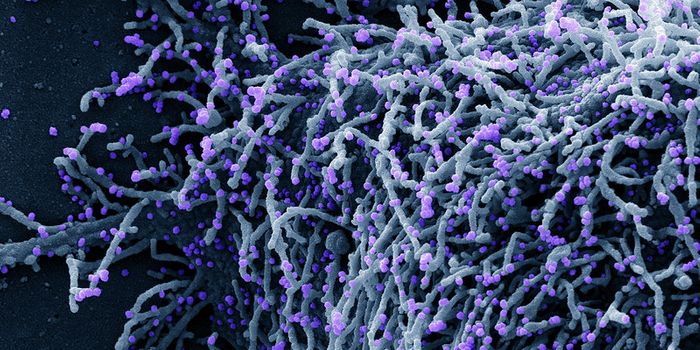

SEP 08, 2024MicrobiologySARS-CoV-2, the pandemic virus that causes COVID-19, has mutated endlessly since it burst on the scene in late 2019. An ...

AUG 27, 2024MicrobiologySince the start of the COVID-19 pandemic, the virus that causes the illness - SARS-CoV-2 - has had a practically infinit ...